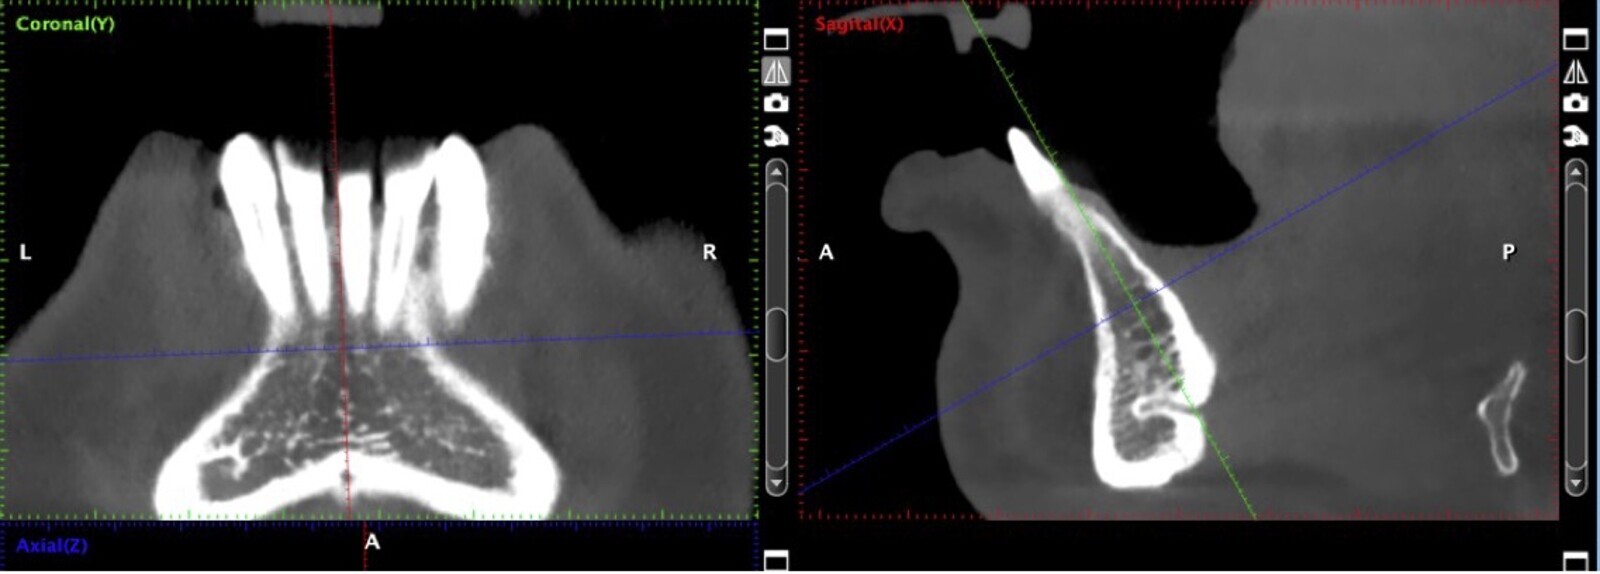

Figura 2. Evaluación de la tomografía computarizada donde se observa la presencia de un conducto vascular de riesgo a ser considerado.

Si la zona donadora es la sínfisis mentoniana, se deben tomar en cuenta los límites de seguridad para la extracción del injerto, que son 5 mm alejado de los ápices, y 5 mm alejado del agujero mentoniano (Figuras 2 y 3).